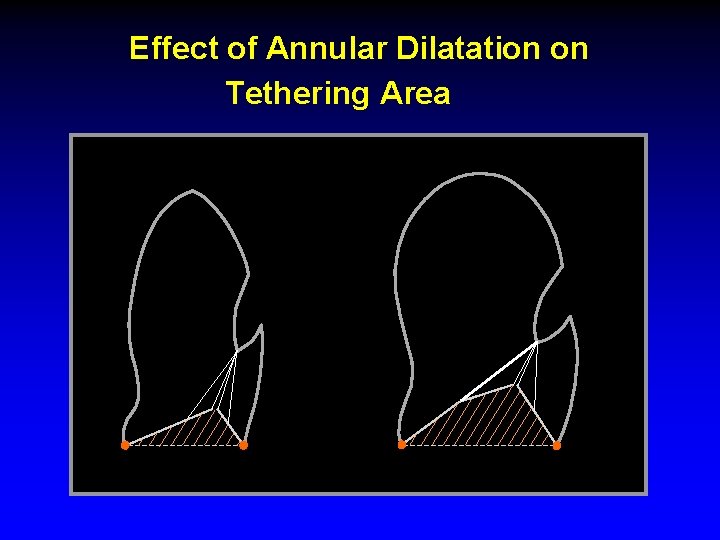

Effect of Annular Dilatation on Tethering Area MROP 340

Ischemic Mitral Regurgitation Mechanisms • Dislocation of papillary muscles • Increased tenting length and area • Antero-posterior dilatation of the MV annulus A-P dilatation of the mitral annulus can determine the degree of MR, even if no anomaly of the mitral leaflets exists • Kinetics of MV annulus during cardiac cycle • Intraventricular synchrony/dyssynchrony • Atrio-ventricular synchrony